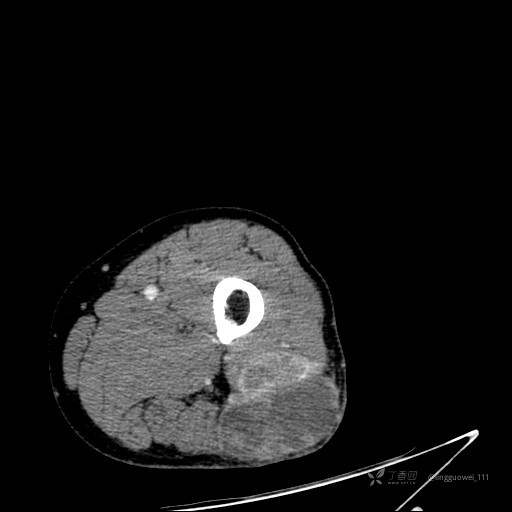

患者性别:男,85岁。发现大腿软组织肿块1年,增大3月,良性还是恶性?只有CT,能诊断正确吗?

平扫